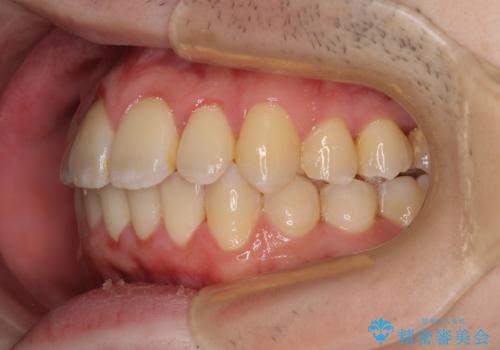

全顎的なクロスバイト 補助装置を用いてワイヤー矯正

- 八重歯や奥歯の噛みにくさを気にして来院された患者様です。

前歯のクロスバイトや八重歯の他に、左右最後臼歯のシザーズバイト(鋏状咬合)が認められました。

シザーズバイト改善のために補助装置を使用しながら、ワイヤー装置にて全体の歯列を整えることとしました。